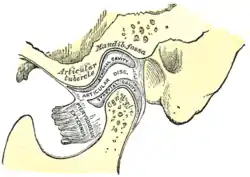

Articular disc

The unique feature of the temporomandibular joint is the articular disc. The disc is composed of dense fibrocartilagenous tissue that is positioned between the head of the mandibular condyle and the mandibular fossa of the temporal bone. The temporomandibular joints are one of the few synovial joints in the human body with an articular disc, another being the sternoclavicular joint. The disc divides each joint into two compartments, the lower and upper compartments. These two compartments are synovial cavities, which consist of an upper and a lower synovial cavity. The synovial membrane lining the joint capsule produces the synovial fluid that fills these cavities.[2] The disc is biconcave in shape. The anterior portion of the disc serves as the insertion site for the superior head of the lateral pterygoid. The posterior portion attaches to the temporal bone. Both upper and lower compartments do not communicate with each other unless the disc is damaged.[3]

The central area of the disc is avascular and lacks innervation, thus getting its nutrients from the surrounding synovial fluid. In contrast, the posterior ligament and the surrounding capsules along have both blood vessels and nerves. Few cells are present, but fibroblasts and white blood cells are among these. The central area is also thinner but of denser consistency than the peripheral region, which is thicker but has a more cushioned consistency. The synovial fluid in the synovial cavities provides nutrition for the avascular central area of the disc. With age, the entire disc thins and may undergo the addition of cartilage in the central part, changes that may lead to impaired movement of the joint.[2] The synovial membrane covers the inner surface of the articular capsule in the TMJ, except for the surface of the articular disc and condylar cartilage.[4]

The lower joint compartment formed by the mandible and the articular disc is involved in rotational movement—this is the initial movement of the jaw when the mouth opens. The upper joint compartment formed by the articular disc and the temporal bone is involved in translational movement—this is the secondary gliding motion of the jaw as it is opened widely.[3]

In some cases of anterior disc displacement, the pain felt during movement of the mandible is due to the condyle compressing this area against the articular surface of the temporal bone.

Each temporomandibular joint is classed as a "ginglymoarthrodial" joint since it is both a ginglymus (hinging joint) and an arthrodial (sliding) joint.[13] The condyle of the mandible articulates with the temporal bone in the mandibular fossa. The mandibular fossa is a concave depression in the squamous portion of the temporal bone.

These two bones are actually separated by an articular disc, which divides the joint into two distinct compartments. The inferior compartment allows for rotation of the condylar head around an instantaneous axis of rotation,[14] corresponding to the first 20mm or so of the opening of the mouth. After the mouth is open to this extent, the mouth can no longer open without the superior compartment of the temporomandibular joints becoming active.

At this point, if the mouth continues to open, not only are the condylar heads rotating within the lower compartment of the temporomandibular joints, but the entire apparatus (condylar head and articular disc) translates. Although this had traditionally been explained as a forward and downward sliding motion, on the anterior concave surface of the mandibular fossa and the posterior convex surface of the articular eminence, this translation actually amounts to a rotation around another axis. This effectively produces an evolute which can be termed the resultant axis of mandibular rotation, which lies in the vicinity of the mandibular foramen, allowing for a low-tension environment for the vasculature and innervation of the mandible.[14]